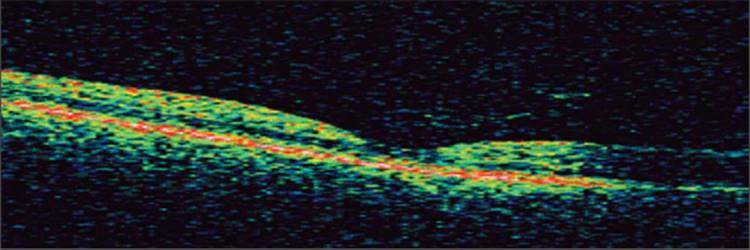

Displayed in Figure 130.2a is a cross-sectional image of the posterior pole in a normal eye obtained on the Stratus OCT-III machine. By convention the vitreous cavity is superior and the external layers of the retina and choroid are inferior. Figure 130.2b is an ultrahigh-resolution scan of a normal retina, which demonstrates much more distinction between structural elements within the retina.

FIGURE 130.2 (a) Normal retinal anatomy. Notice how the NFL increases in thickness nasally toward the optic nerve (right side of image). Cellular layers, such as the ganglion cell layers and the inner and outer nuclear layers have less intense backscattering due to the density and orientation of their respective elements. Layers with more intense reflectivity include the RPE/Choriocapillaris, the junction between the inner and outer segments of the photoreceptor layer, the inner and outer plexiform layers, as well as the NFL. Axial resolution is 8 ?m. (b) Ultrahigh-resolution OCT of a normal retina. Axial resolution is 2 ?m. Notice the greater ability to identify retinal structures/layers.

Photo courtesy of Dr JS Duker.